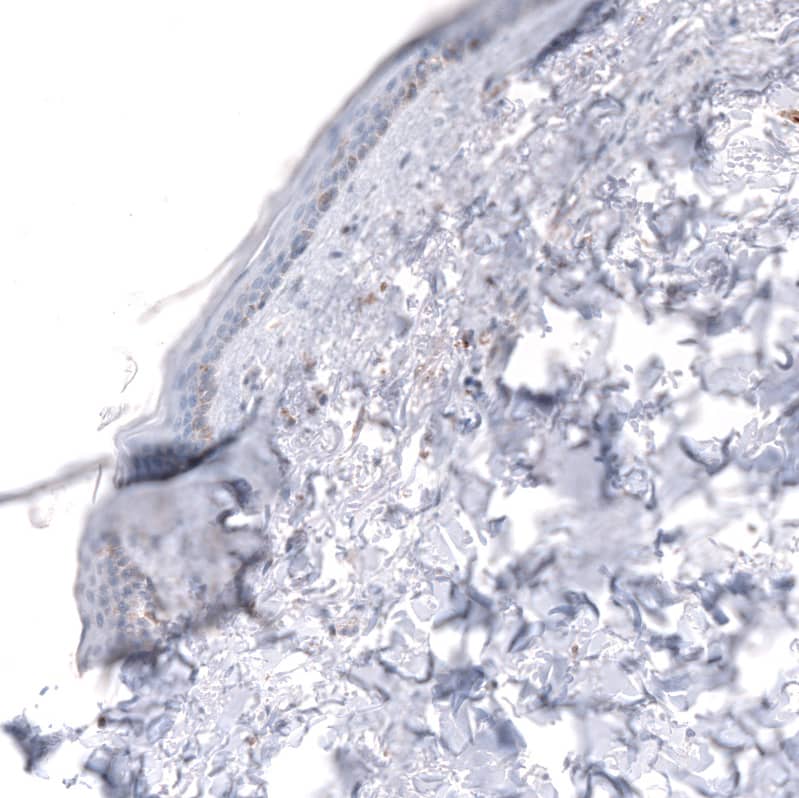

Staining of human skin shows negative to very weak positivity in squamous epithelial cells.